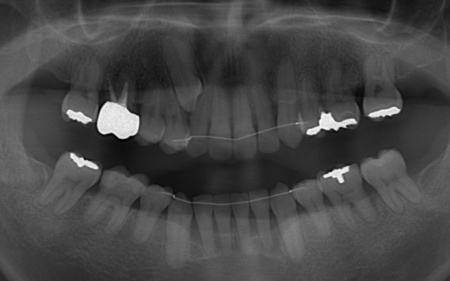

| カウンセリング | 拝見したところ、上下の歯は、ずれたりねじれたりしてデコボコに生えており、著しく歯並びが乱れていました。

またレントゲン撮影をして確認すると、右上前歯は顎の骨の中に埋まっている骨性埋伏(こっせいまいふく)の状態でした。 さらに、左下奥歯は重度の歯周病であり、歯を支えている骨が一部溶けていることが判明しました。 以上のことから、歯並びを整える矯正治療と歯周病の治療を併せて行う必要があると診断しました。 |

①抜歯をしてから歯並びを整える「抜歯矯正」 今回のケースでは、左上下の奥歯各1本(第3大臼歯)、右下の奥歯1本(第3大臼歯)、左上下と右下の奥歯各1本(第1小臼歯)の計6本の抜歯が必要です。 また、奥歯の噛み合わせは正常だったことから、それを維持しながら歯並びを整えるために以下の方法を採用します。 ②矯正治療後、歯周病を発症している左下奥歯(第1大臼歯)を温存するために、失われた骨や歯茎を再生する「歯周再生療法」を行う まずは歯の移動スペースを確保するために、計6本の歯を抜きます。 矯正治療終了後、歯の後戻りを防ぐため、上下前歯の裏側にワイヤーを接着して固定させる「フィックスリテーナー」を装着しています。 その後、左下奥歯に歯周再生療法を行って歯周病が改善したことを確認し、治療を終了しました。 |